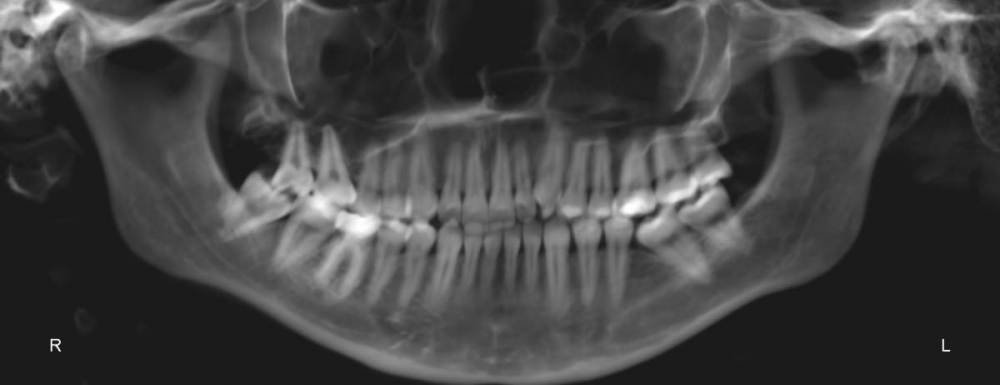

На консультации у ортодонта был поставлен диагноз : Нейтральное соотношение челюстей с тенденцией к дистальной окклюзии. Глубокая резцовая окклюзия.

Врач предложил установить безлигатурную брекет систему , вообщем-то , я была согласна, но замена имплантами 2 отсутствующих шестерок  меня немного пугала.т.к шестерки были удалены достаточно в раннем возрасте соседние зубы заняли их место и визуально это было почти не заметно .При всем  этом , у меня есть все восьмерки ,соответственно , перед установкой БС их так же нужно будет удалить(

Так вот , у меня возник вопрос, возможно ли стянуть  зубы в ровную окклюзию при помощи БС вместе  с 7(Заменяющей место 6) и 8 ?

То есть , возможно ли как-то восстановить центральную окклюзию и, в целом, сделать красивую улыбку не применяя имплантацию ?).